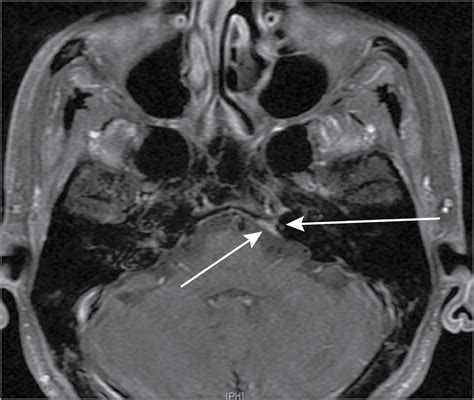

Abducens Nerve Palsy | Radiology Reference Article | Radiopaedia.org

abducens palsy radiopaedia

A Common Cause Of Cranial Nerve VI Palsy—Hidden In Plain Sight: A

nerve cranial palsy